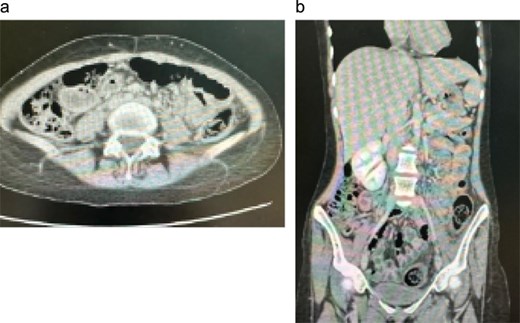

On presentation to our center, she appeared cachectic with persistent neurological impairment. Abdominal examination revealed a soft, lax abdomen without localized tenderness or palpable masses. Laboratory investigations showed systemic inflammation and anemia, with an erythrocyte sedimentation rate of 56 mm/h, a white blood cell count of 13.5 × 109/L, a C-reactive protein of 205 mg/L, and a hemoglobin of 8.9 g/dL. Abdominal MRI demonstrated extensive circumferential thickening of the rectum and sigmoid colon with widespread peritoneal disease, bilateral mild hydronephrosis, and a loculated fluid collection in the upper pelvis (Fig. 3). The differential diagnosis included atypical infections such as tuberculosis and fungal disease (basidiobolomycosis or actinomycosis), as well as adenocarcinoma and lymphoma. Tumor markers and microbiological studies were negative.

The patient was commenced on intravenous voriconazole 200 mg twice daily on 26 June 2023 and was transitioned to oral voriconazole 200 mg twice daily in January 2024 for a planned 1-year course. She exhibited marked clinical and radiologic improvement, with follow-up computerized tomography scan shown in Fig. 5, showing regression of rectosigmoid and peritoneal disease, and was discharged home with planned outpatient follow-up. Subsequent surveillance imaging demonstrated recurrence of rectosigmoid and pelvic disease; however, she remains clinically asymptomatic and continues oral voriconazole under close multidisciplinary review to determine the need for treatment escalation or additional therapeutic interventions.

Follow-up contrast-enhanced CT abdomen and pelvis. (a) Axial image demonstrating resolution of the previously noted circumferential rectosigmoid wall thickening and pericolic inflammatory changes, with no residual pelvic mass or collection. (b) Coronal reformatted image confirming marked regression of rectosigmoid and peritoneal disease, consistent with a favorable radiologic response to prolonged voriconazole therapy.

She was discharged home in stable condition. Subsequent follow-up imaging demonstrated recurrence of rectosigmoid and pelvic disease; however, she remains free of gastrointestinal symptoms and continues on oral voriconazole under close multidisciplinary follow-up to assess the need for treatment escalation or adjunctive interventions.